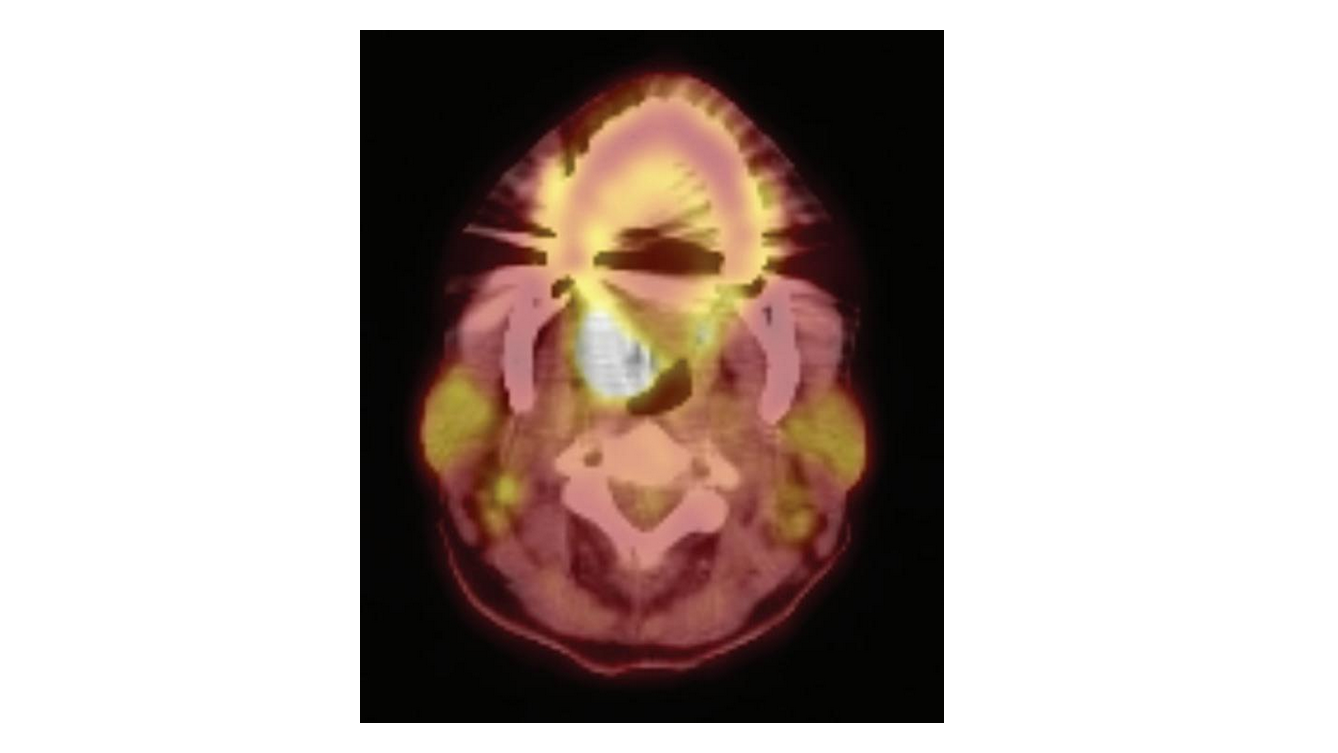

Based on history, clinical examination, and previous diagnosis from a skin biopsy, it was determined that the oral lesions were consistent with MMP. A review of systems revealed dysphagia, odynophagia, and nasal bleeding, and routine head and neck examination revealed a unilaterally large palatine tonsil. The clinical findings and results of computed tomographic imaging dictated a biopsy of the right tonsil, and immunohistochemical analyses of the biopsy specimen revealed markers consistent with MCL, which was later determined to be stage III (Figure).